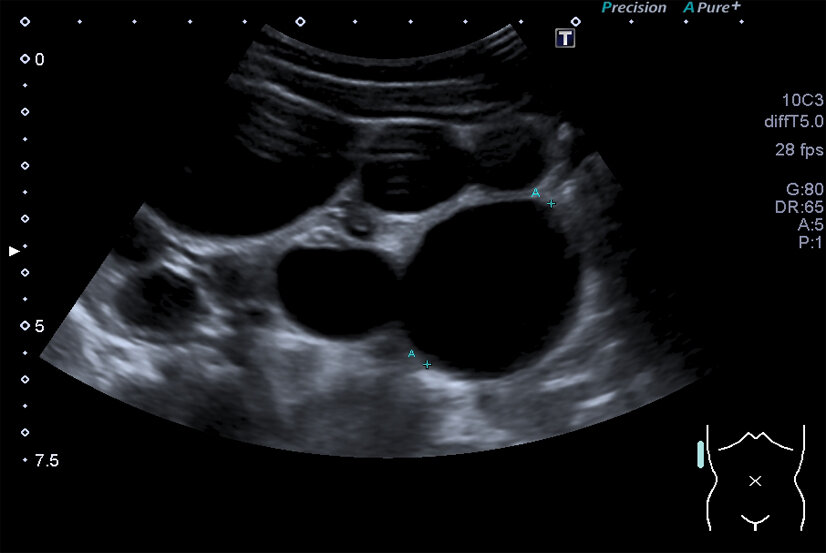

Multizystische Niere. Man erkennt die regellose Anordnung der verschieden großen Zysten. Reguläres Nierengewebe ist nicht erkennbar. (Foto: Roselieb)